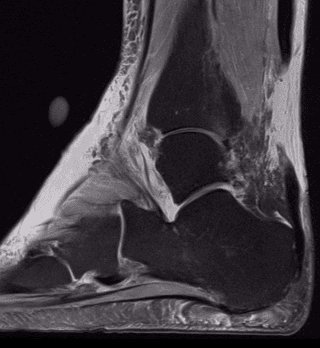

La diagnosi può essere approfondita con esami strumentali, quali l’ecografia e la risonanza magnetica.

Se la diagnosi clinica sembra abbastanza facile, e viene spesso completata dalla risonanza magnetica e dall’ecografia, bisogna ricordare che nel 20% dei casi questa lesione non viene riconosciuta, il che porta ad un aggravamento del quadro clinico, dovuto alla retrazione tendinea, che aumenta progressivamente nei primi 15 giorni seguenti alla lesione.